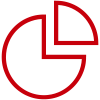

This structure is inspired by the detection model of the cardiac marker ŌĆö troponin, where the detection and capture antibodies work together to capture antigen complexes. The combination of the beveled, flipped wooden pieces reproduces the dynamic, folded structure of the proteins.

Schematic illustration of cTnI testing system

After performing hundreds of screening experiments, HyTest finally obtained a brand-new pairing model, which marks a new height in sensitivity. Improved sensitivity will expand the field of vision to help detect earlier changes, meaning the possibility of discovering even more clinical applications.